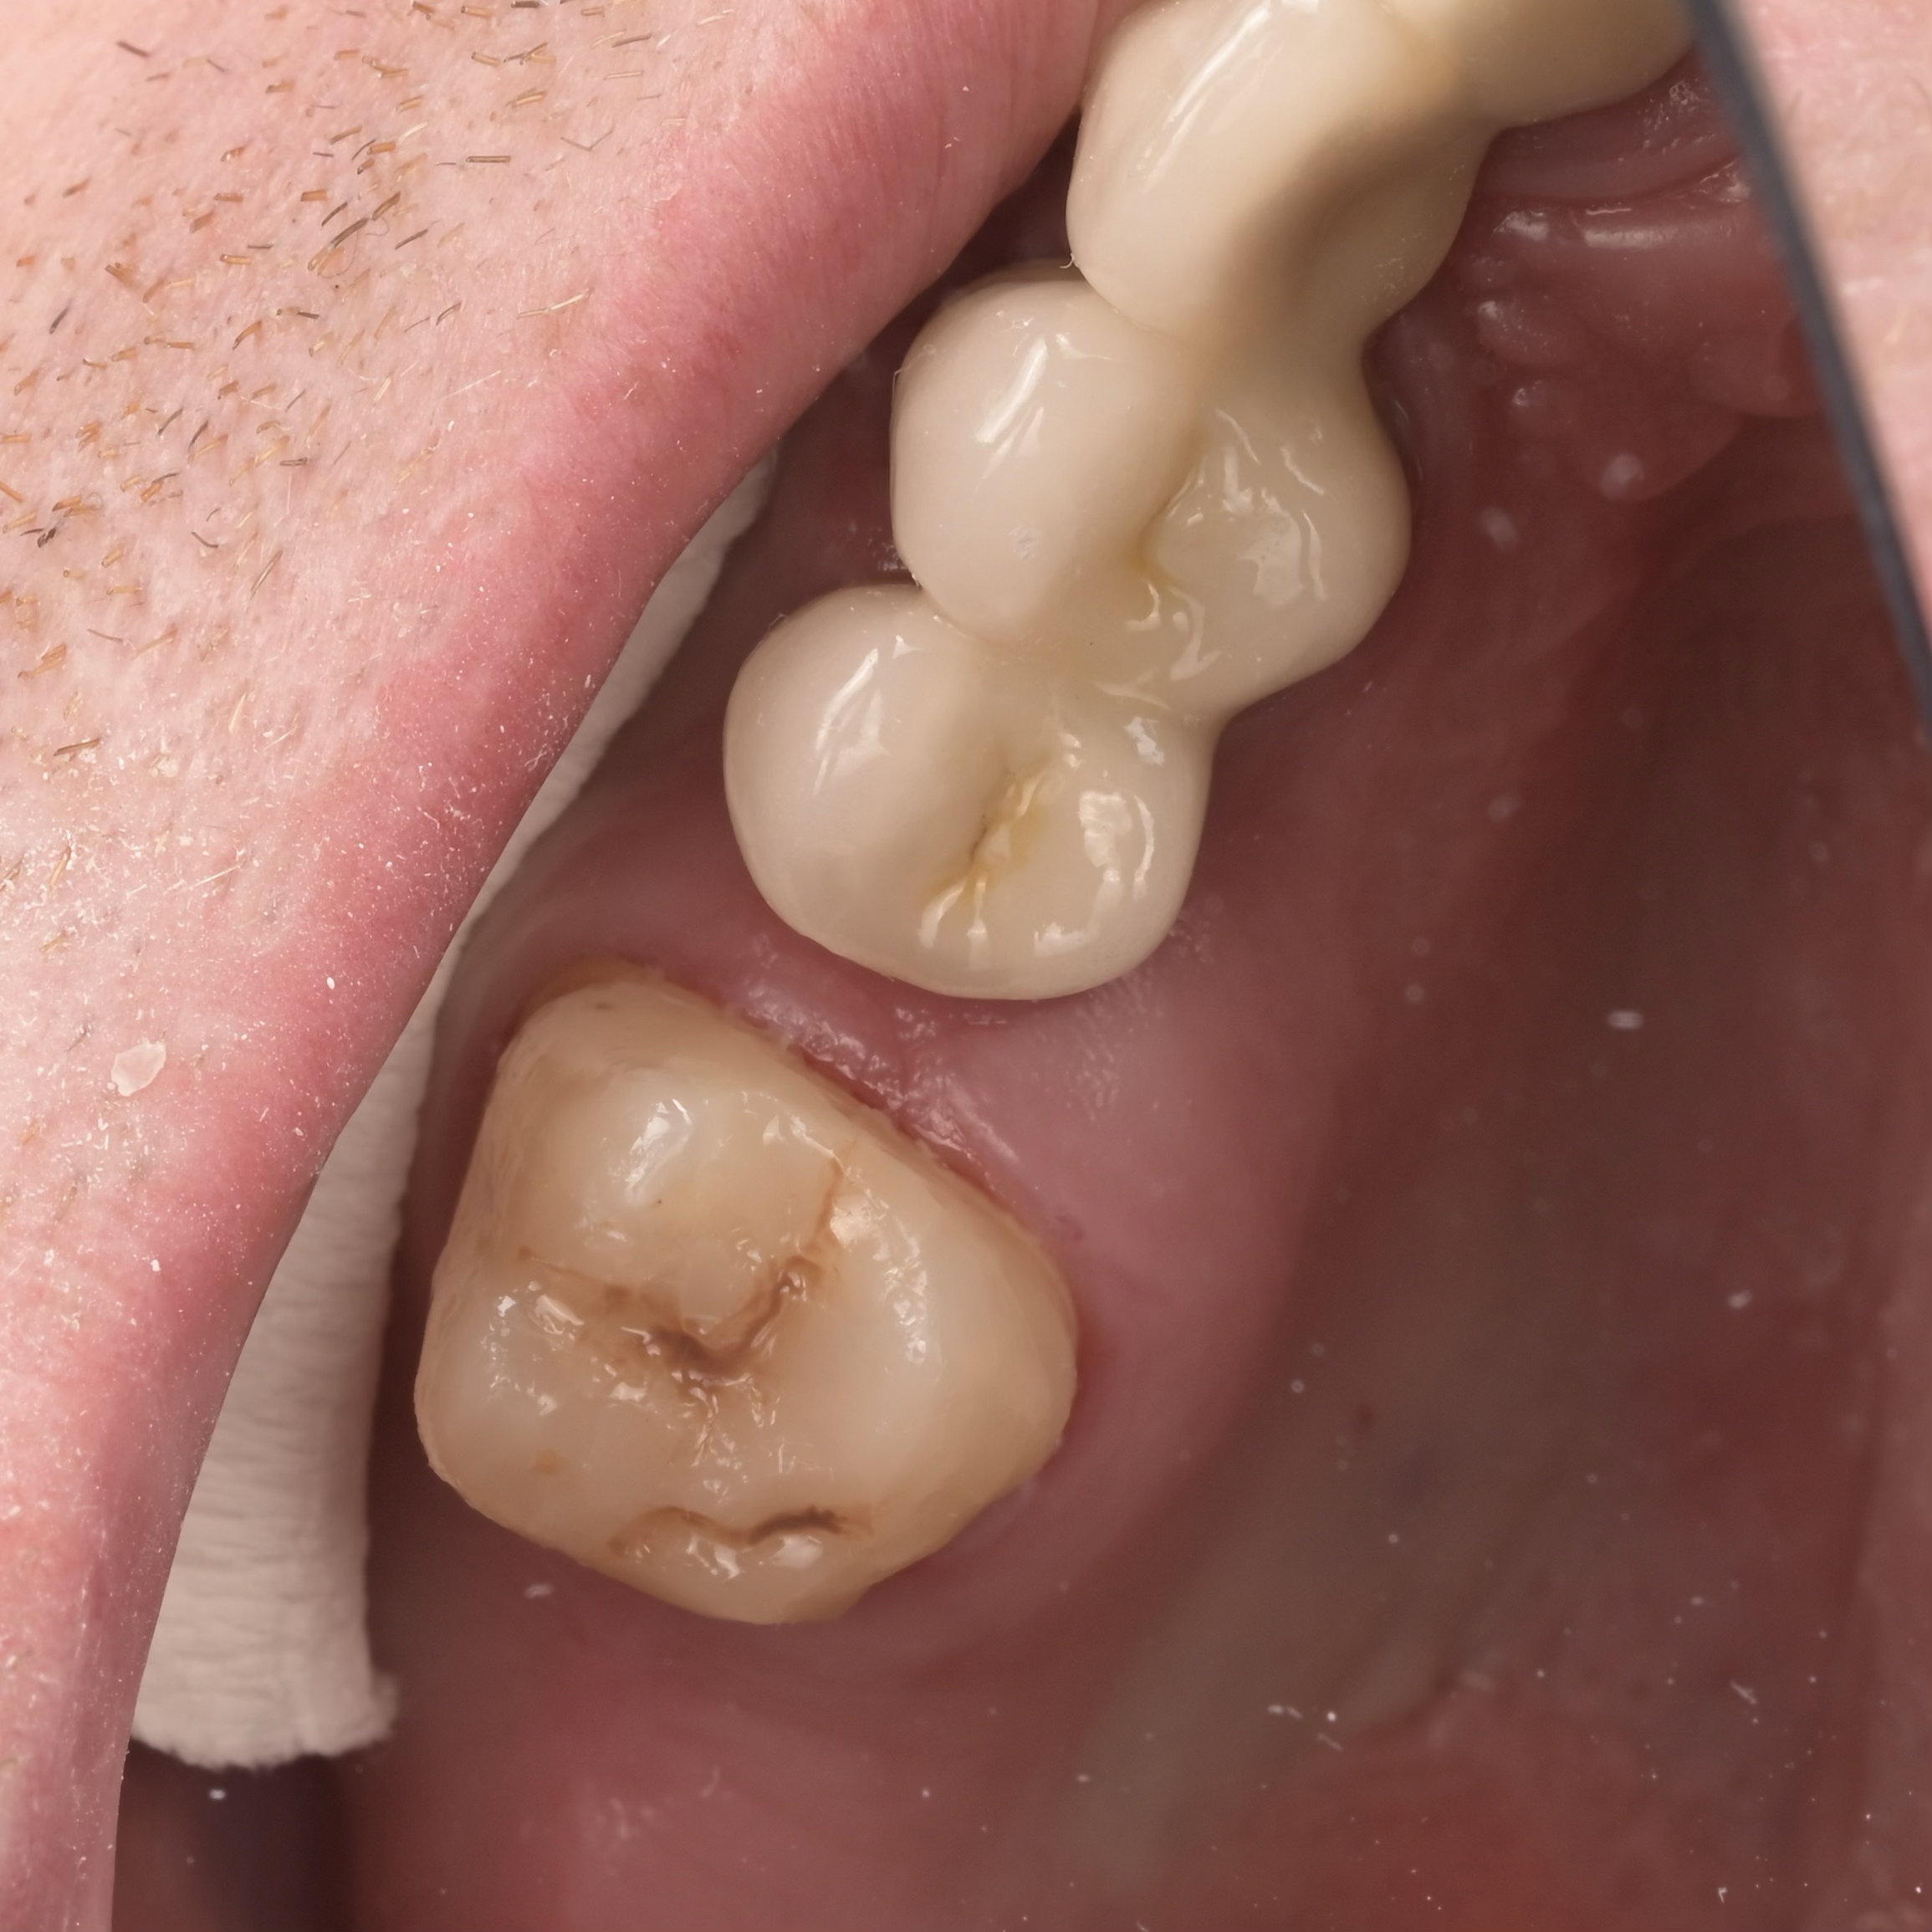

A biomimetikus fogászat egy modern megközelítés, melynek célja, hogy a fogak helyreállítását a fogorvos a természetes fog szerkezetét utánozva végezze el. A módszer kulcsa, hogy a fogat a lehető legkevésbé invazív módon kezelje, maximalizálva a megmaradt egészséges fogszövetet.

Célja, hogy az elkészült tömések és betétek (inlay, onlay) ugyanolyan erősek és rugalmasak legyenek, mint a természetes fog.

Ennek eléréséhez speciális ragasztási technikákat és bio-kompatibilis, üvegszál-erősítésű anyagokat használnak, melyek szorosan kötődnek a foghoz.

A hagyományos koronázással szemben, ahol sok ép foganyagot kell eltávolítani, a biomimetikus eljárásnál csak a sérült részeket távolítják el.

Ez segít megelőzni az úgynevezett „mély tömések” okozta gyökérkezelési szükségletet, mivel az ideg a fogban kevésbé sérül.

A megmaradó erős fogszövetnek köszönhetően a helyreállított fogak sokkal ellenállóbbak a repedésekkel és töréssel szemben.

A rágóerők egyenletesebben oszlanak el, így a fogat kevesebb stresszhatás éri rágás közben.

Ez a megközelítés hosszú távon stabilabb és tartósabb eredményt biztosít, csökkentve a jövőbeni fogászati beavatkozások szükségességét.

Összefoglalva: Az így elkészült tömések időtállóbbak, pontosabbak és jobban védik a megmaradt foganyagot, mint a hagyományos technikával elkészített tömések, a kutatások alapján, ez a jelenlegi ismereteink szerinti legmodernebb, evidence-based eljárás.